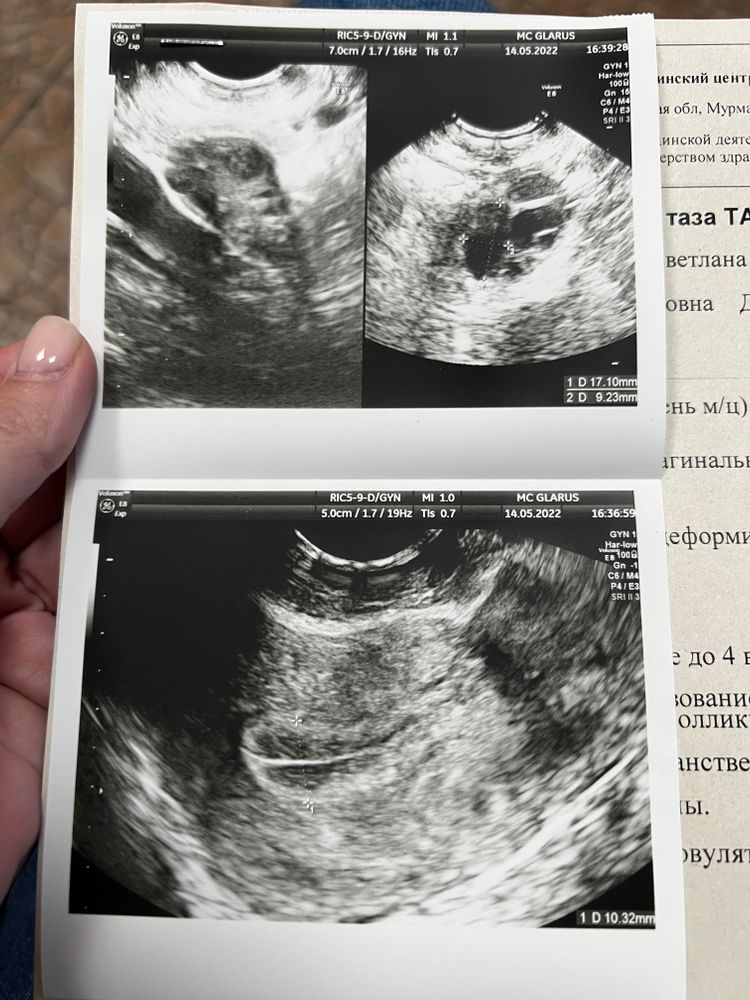

Итак, позавчера был фолликул около 19 мм, вчера укол хгч 5000.

Сегодня на УЗИ фолликула нет , спасшиеся стенки, желтого тела тоже ещё нет,вроде признаки овуляции. Но нет и жидкости нигде!!!